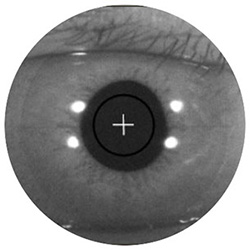

Автоматичне відстеження на передній ділянці ока

Після позиціонування приблизно на центр зіниці система автоматично виявляє є та підтримує точний центр, навіть коли пацієнт рухає оком або моргає.

Автоматична оптимізація зображення

Вбудовані функції автоматичного фокусування та К-затвору автоматично визначають найвищу якість сигналу для найкращих можливих результатів експертизи.